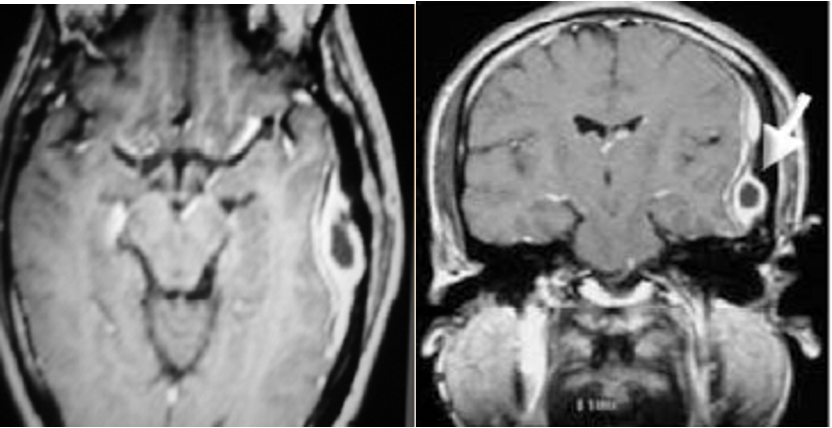

Epidural Abscess

- CT scans reveal the abscess as well as the middle ear pathology.